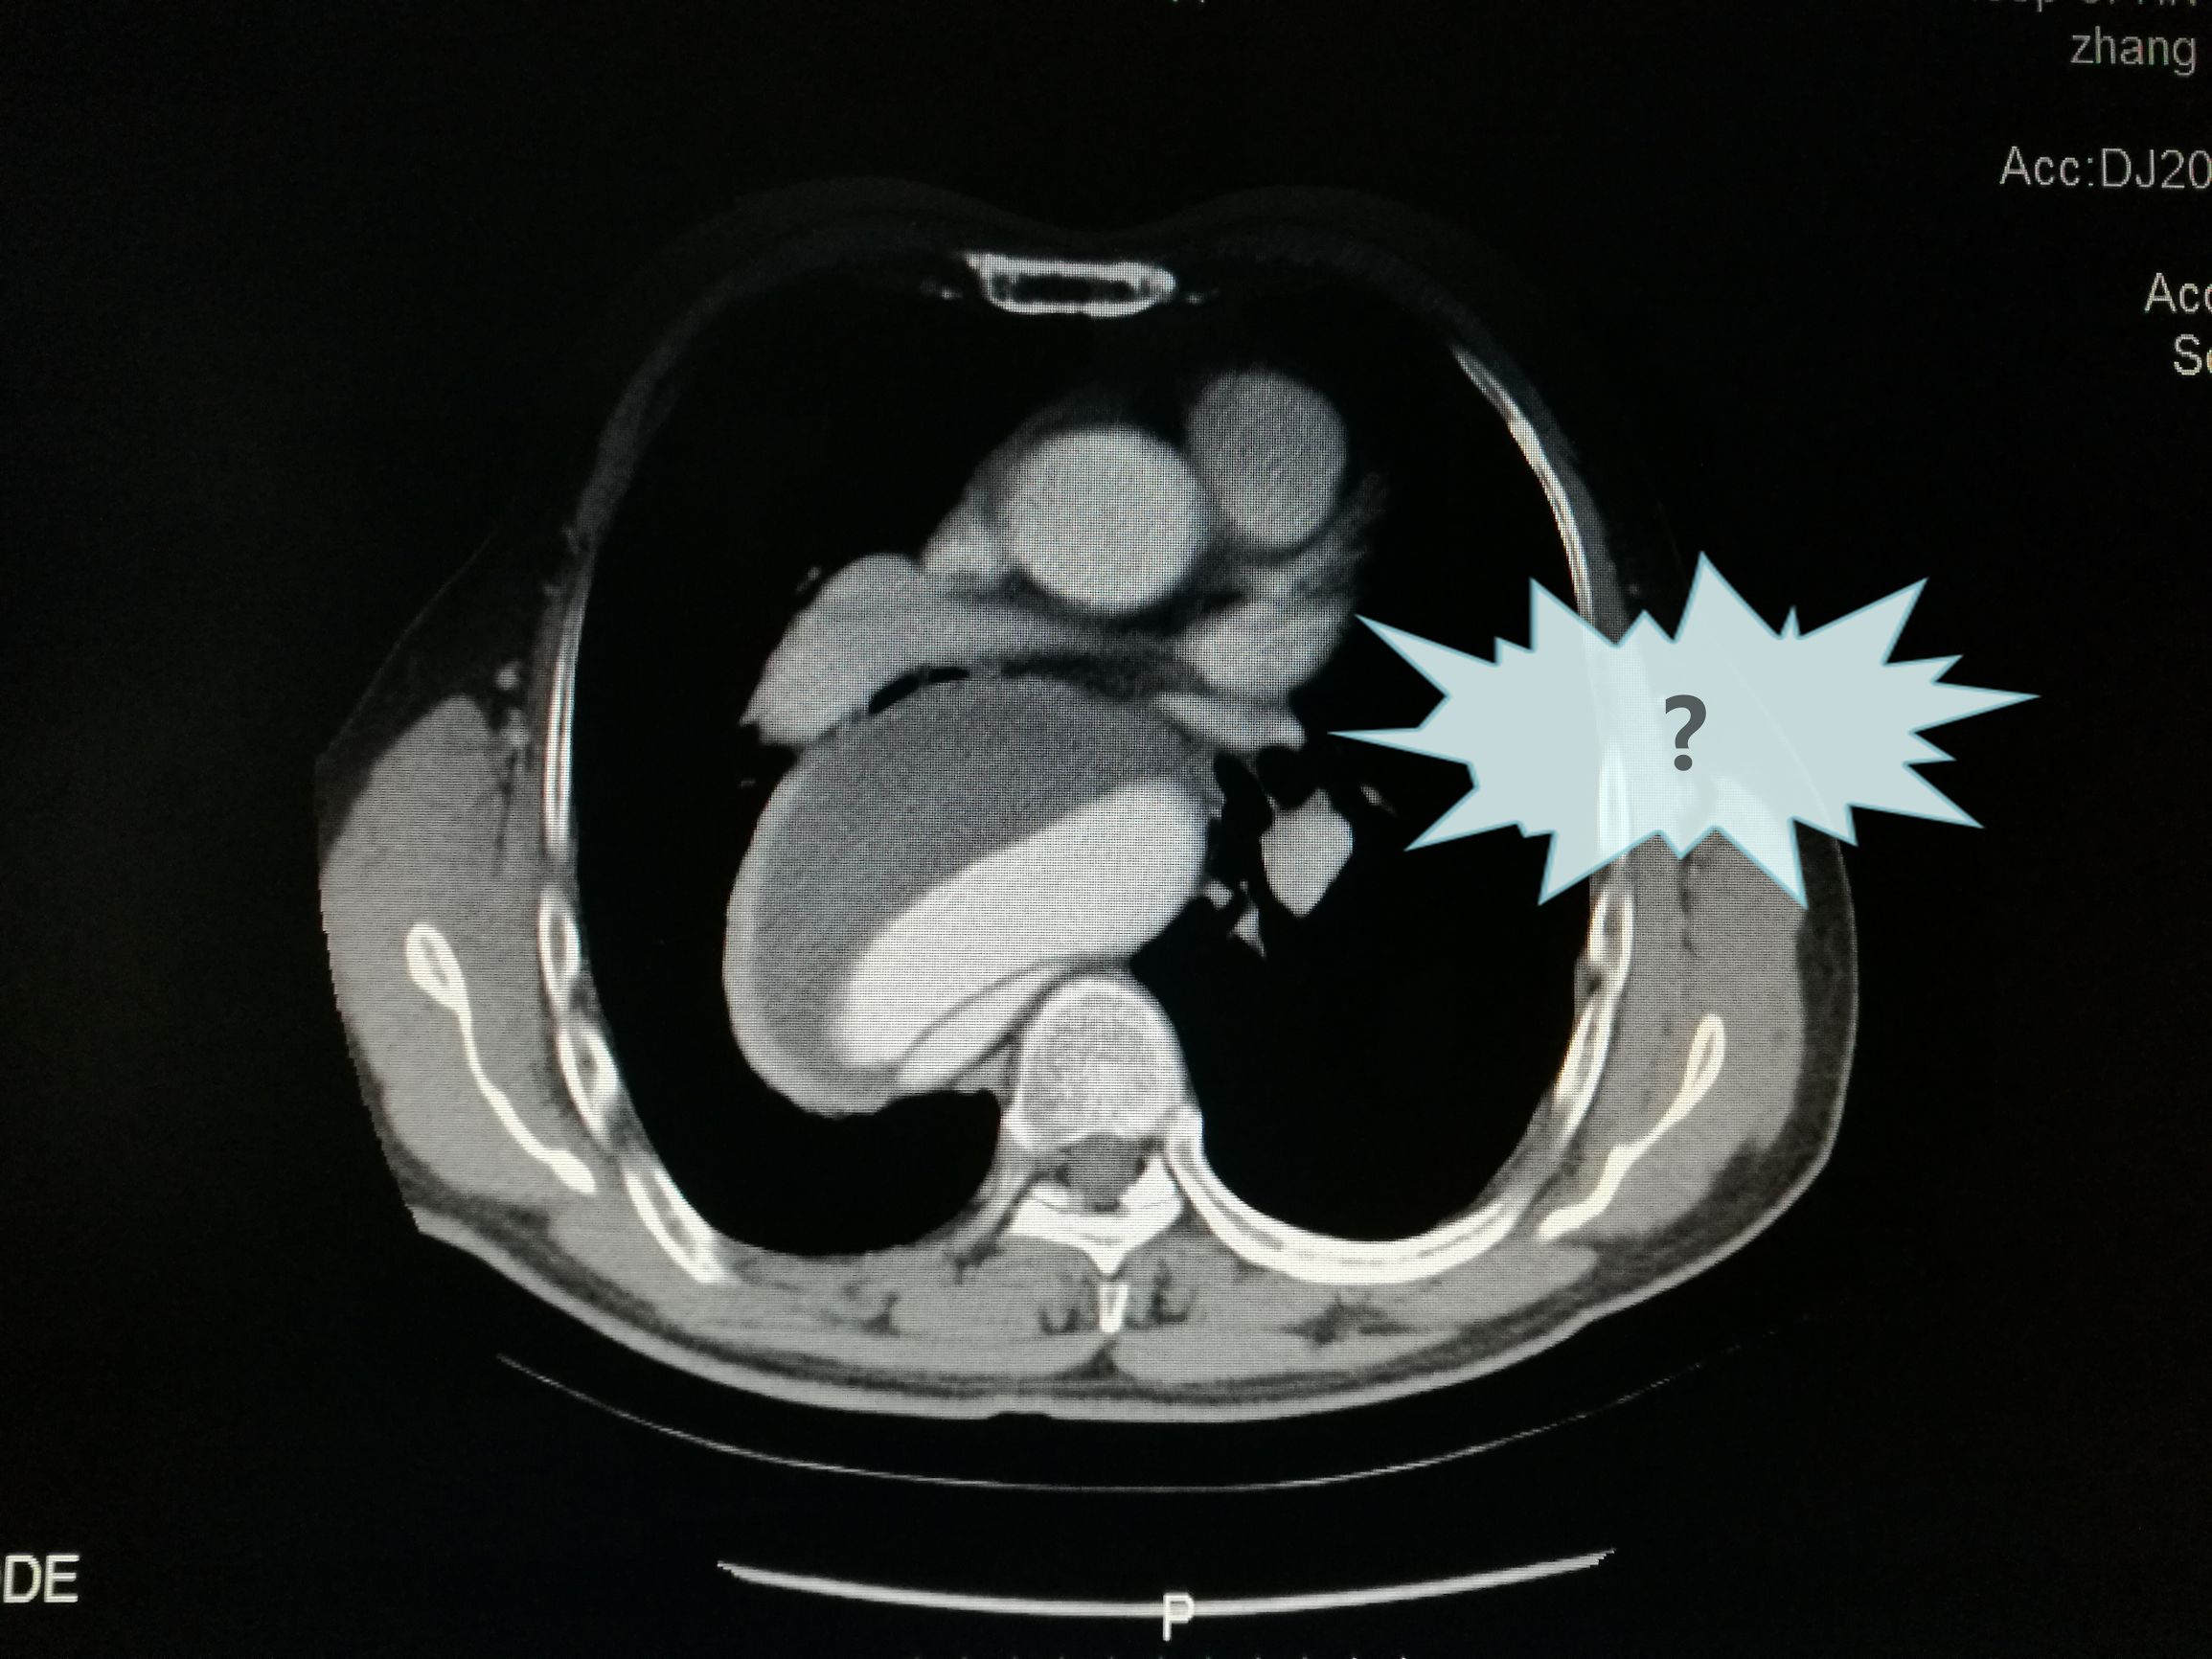

此例患者进行发病时未能确诊,进入慢性期后假腔扩张瘤样变。在CT的部分层面,食道受压看不到。重建影像可见假腔扩张,动脉扭曲。

慢性夹层能封堵如此完美的少,假腔压迫导致吞咽困难的也不多,慢性夹层血管扭曲严重,手术难度较大。血管病争取早发现早治疗效果好。